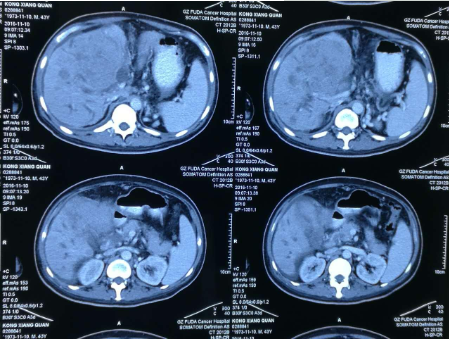

孔祥泉,男性,43岁,因皮肤发黄、肝区不适一个月,各种检查结果很不乐观。MR检查见:“S4/8肝内多发结节及团块(最大102mm*81mm),考虑肝癌合并子灶,侵犯肝门区胆管,门静脉主干及分支、肝右静脉受压、管腔变窄,肝内胆管扩张。胆囊增大并壁周水肿。肝硬化、脾大、少量腹水,食管下段、胃底及脾周静脉曲张,肝门区、门腔间隙及腹主动脉旁淋巴结(百度搜索:广州复大肿瘤医院)。